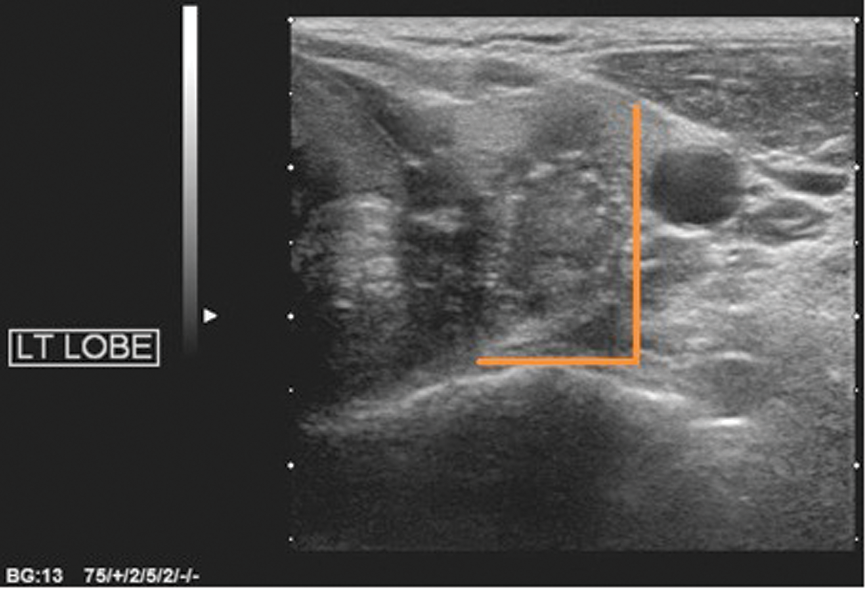

There are a few important points to consider: it is papillary cancer that is accounting for the increase in thyroid cancer incidence, and the four US features used in the Kim and AACE criteria are the cardinal features of papillary cancer (Figures 1-4). For high sensitivity, the Kim Criteria should be used, for high specificity, AACE criteria. The use of nodule size reduces sensitivity and specificity quite markedly.

Figure 4: Taller-than-wide (AP>TR in transverse plane).